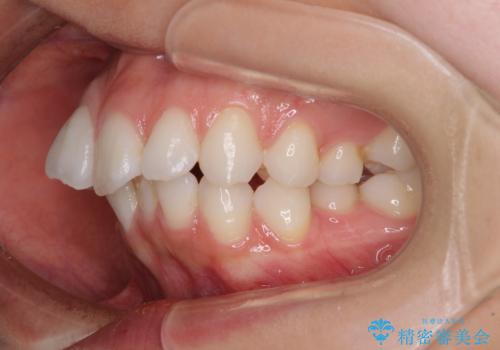

- 口元の突出感を気にして来院された患者様です。

左右ともに奥歯の咬み合わせに問題があり、上顎臼歯が前方位にある状態で、結果として上顎前歯全体が前方位かつ叢生になっていました。